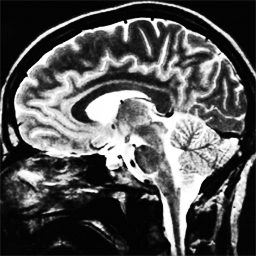

As can be seen in the experiments with one training image, the spatially adapted does not only capture inhomogeneities in the noise, but also adapts to the scale of structures in the underlying image. Learning one fixed parameter, therefore, for more than one image seems counterintuitive since these local adaptions will change in each image. In the following experiment we argue, however, that if the training set features images with sufficiently similar content as well as with similar and heterogenous noise properties, as might be the case for MRI scans of brains, then the learned, spatially-adapted still outperforms a learned that is constant. To verify this, we compute the optimal functional parameter from a training set of 10 pairs , . The images (of size ) were taken from the OASIS online database. A Gaussian noise with was distributed on the images, and in the areas marked by red, additional noise with was imposed (to all noisy images at the same location).

In the last experiment we compare the results of our optimal learning approach with the ones obtained with the spatially adapted total variation method (SA-TV) proposed in [10]. For the comparison, we apply the optimal spatially-dependent parameter computed in the previous experiment (see Figure 4.8) to a different brain scan, not included in the training set.